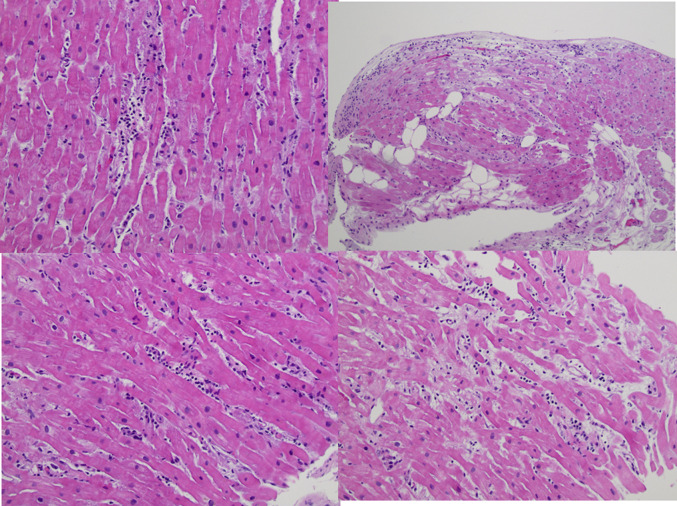

On hospital day 24, a repeat echocardiogram demonstrated improvement in her left ventricular systolic function with an ejection fraction of 50%-55%, normal left ventricular size, and reduced left ventricular wall thickness. Given stable and acceptable hemodynamics, she was started on metoprolol succinate, isosorbide dinitrate, and hydralazine. Cardiac magnetic resonance (CMR) was ordered to confirm the diagnosis of myocarditis and to assess more fully left and right ventricular systolic function. Diffuse hyperintensity on T2 mapping (up to 67 milliseconds, normal <52 milliseconds) suggestive of myocardial edema or inflammation was observed (Figure 3 , Video 3). The myocardial extracellular volume fraction was significantly elevated at 39% (normal <29%), indicative of diffuse interstitial expansion. LVEF and right ventricular ejection fraction were 45% and 33%, respectively, with normal biventricular size. Right heart catheterization and endomyocardial biopsy (EMB) were also performed to exclude granulomatous myocarditis, given the arrhythmia burden. The biopsy showed scattered perivascular and interstitial inflammatory cells consisting of CD3-positive T-lymphocytes, CD20 positive B-lymphocytes, and histiocytes, along with interstitial and myocyte injury, suggestive of acute viral myocarditis. Viral immunostains for herpes simplex, adenovirus, and cytomegalovirus were negative. Congo red and iron stains were negative. There was no evidence of multinucleated giant cells, eosinophils, or granulomas (Figure 4 ).

Figure 4.

Endomyocardial Biopsy

Endomyocardial biopsy showing scattered perivascular and interstitial inflammatory cell infiltrates, interstitial and myocyte injury, suggestive of acute myocarditis. Predominant CD3 T-lymphocytes fewer CD20 B-lymphocytes and CD68 histiocytes. Viral immunostains for herpes simplex virus, adenovirus, and cytomegalovirus were negative.

Role of biopsy

Traditionally, EMB has been considered the gold standard for diagnosis in patients with acute myocarditis. In cases of fulminant myocarditis, EMB can help discern the specific etiology and provide additional assistance in guiding therapy.9 In less severe cases of myocarditis, EMB has a lower sensitivity for diagnosis than CMR and is also less likely to inform management.2 , 16 EMB is also limited by low yield because of sampling error and lack of consensus on standard criteria for interpretation.10 , 11 , 16 In our case, EMB helped confirm the diagnosis of post-viral lymphocytic myocarditis, while ruling out alternative etiologies.